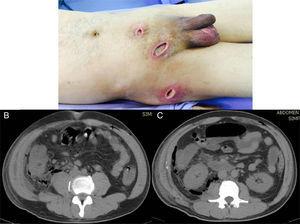

A) Important soft tissue infection is shown that extends from the suprapubic incision to the right inguinal region, and to the right scrotal region and flank, all with significant purulent matter. B) Tomographic image showing the retroperitoneal abscess extending proximally until reaching the costal ridge, with the presence of gas in its entire extension. C) Image showing the retroperitoneal abscess at the level of the cecum that extended through Toldt's fascia, with the presence of gas at this level.

A 44-year-old man, who came to us from another hospital, had a relevant personal history of long progression type 2 diabetes mellitus that was apparently well controlled, and he had undergone a laparoscopic appendectomy on April 12, 2015 (38 days before we saw him). Phase III acute appendicitis was reported. It was defined as a venous infarction, total wall necrosis, and perforation, with the later formation of a localized abscess. Unfortunately, we had no detailed clinical report on the intraoperative findings or the surgical technique performed (use of antibiotic-impregnated sutures and/or preoperative asepsis and antisepsis measures). However, upon the patient's admission to our hospital, we observed a 3-port approach. One was a transumbilical port, another was at the level of the left flank, and the other was suprapubic. The first 2 had cicatrized, but abundant purulent matter was exuding from the suprapubic port wound. Likewise, we observed 3 other incisions, one at the level of the right inguinal region, another at the ipsilateral scrotal level, and another at the level of the right pelvic limb on the lateral surface of its proximal third, all of which contained abundant purulent matter and had an apparent internal connection (fig. 1A).

Abdominal tomography scan identified a retroperitoneal collection at the level of the right fossa and paracolic gutter that extended into the soft tissues (figs. 1B and C). Exploratory laparotomy revealed an abscess of approximately 80 cc at the level of the retroperitoneum. A sample was taken from it for culturing and it developed Escherichia coli. The abscess was drained, and a closed drain was later placed at that level. The cavity was closed and lavage and soft tissue debridement was carried out, communicating the suprapubic wound and the proximal third of the leg. Access to the entire right paracolic gutter was thus achieved, revealing fasciitis and necrotic tissue. The latter was debrided and a Vacuum Assisted Closure (VAC) system was placed. Two surgical lavages with VAC replacement were later required. Patient progression was very satisfactory and leukocyte in blood (6.06 thousand/μl), procalcitonin (0.08 ng/ml), and C-reactive protein (0.71 ng/dl) values returned to normal. Given the patient's good progression, the surgical wound where the VAC was previously placed was closed and the abdominal drain was removed at 3 weeks, with a minimum serous output (fig. 2).